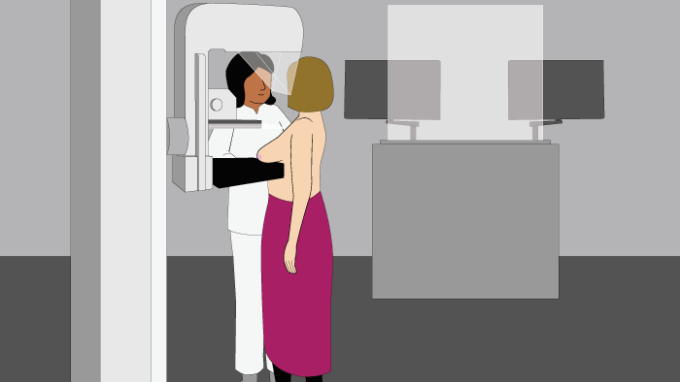

Er was een wachttijd bij de mammapolie, maar dat vond ik niet erg. Onze (schoon)moeder konden we nu in alle rust en kalmte begeleiden naar en tijdens de uitvaart. De dag erna stond mijn date gepland met de tietenplet-machine! Ik zag er tegenop hoor. Het leek mij niets, dat gesjor aan je borst door een vreemde dame. Maar wat moet, dat moet.

Het viel uiteindelijk mee! Het is zeker niet prettig maar echt super pijnlijk was het nou ook weer niet: Je staat ongemakkelijk. Je borst wordt op zo’n ‘tafeltje’ gekleid en dan komt de plexiglas plaat erop. Handmatig geeft de verpleegkundige nog een kleine extra draai aan de plaat en dan gaat de ‘kopieer-machine’ er bovenlangs.

[…] maar gelukkig bleek het een onschuldige cyste (een met vocht gevulde holte). Ik schreef er een blog over en beschreef hoe een mammografie nou in zijn werk […]